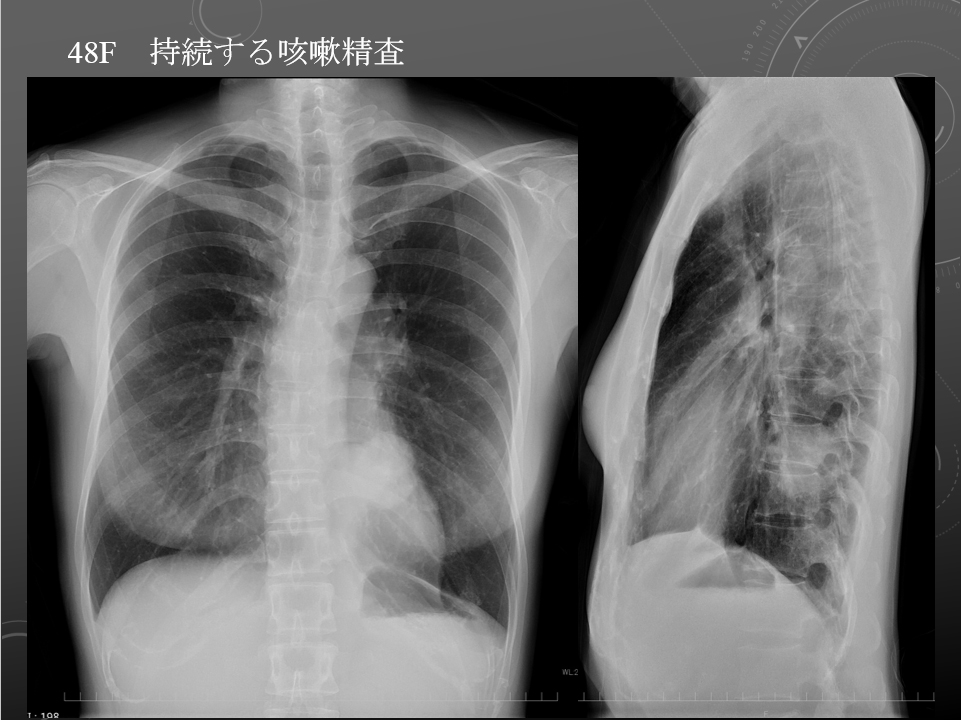

48M 持続する咳嗽精査 左肺下葉原発性肺腺癌